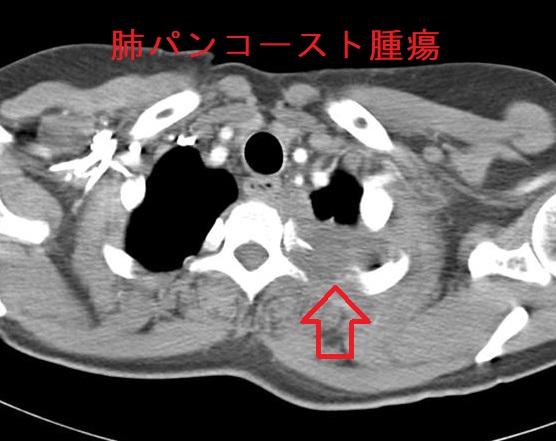

- パンコースト腫瘍(Pancoast腫瘍)

パンコースト型肺癌(Pancoast 型肺癌)は肺尖部浸潤型肺癌で、

- 胸部エックス線にて早期発見難

- 呼吸器症状がない

- 最近は腺癌な割合が増えている